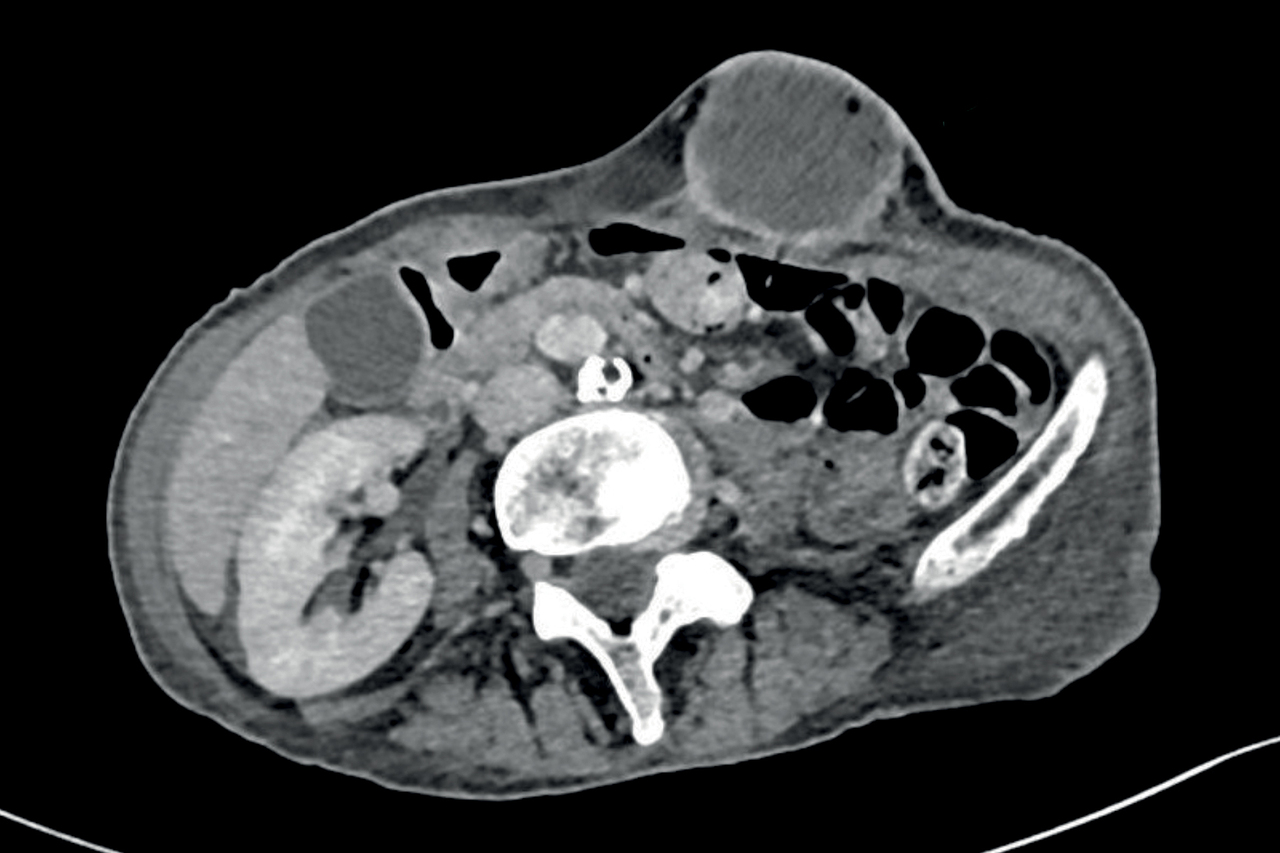

Le scanner montre de multiples formations pariétales et profondes sus- et sous-diaphragmatiques, d’allure tissulaire avec zone centrale liquidienne ainsi qu’une masse parotidienne. La biopsie d’une lésion pariétale met en évidence une métastase d’un adénocarcinome parotidien.